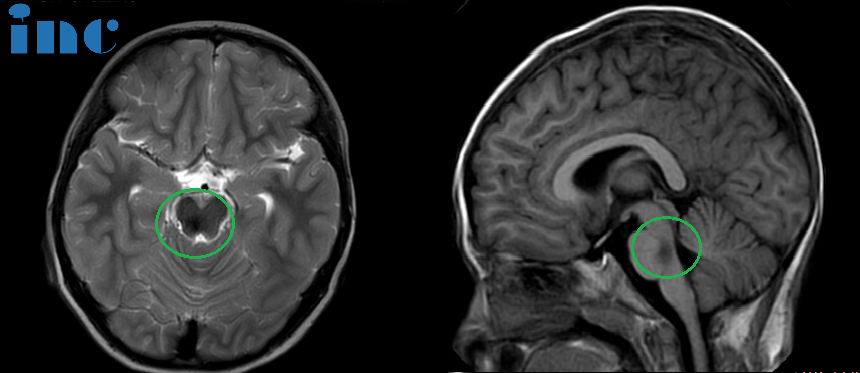

▼术前术后对比图片

术前:脑桥占位。双眼斜视、畏光,面瘫,频发不自主扭头动作,走路稍有不稳。头颅MR(红色区域)显示:脑桥血肿,可见16 x 22 x 21mm肿块,四脑室受压变窄。

术后:头颅MR(蓝色区域)显示小脑半球及脑干形态正常,中线结构居中,原脑桥内团块状信号消失。